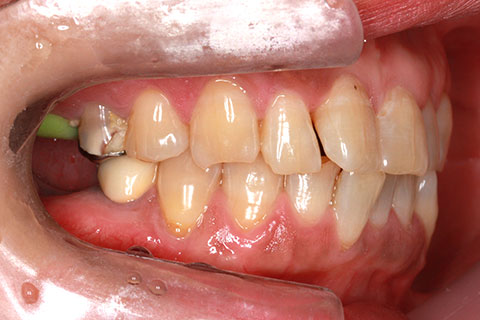

• オールセラミックの症例2

治療前

治療後

年齢・性別

45歳男性

治療期間

2ヶ月

抜歯

なし

治療費

70.4万円

備考

前歯8本の歯列不正によるセラミック治療

治療内容

歯質を削除し、セラミック冠をセメント合着

施術の副作用(リスク)

知覚過敏、歯髄炎、荷重負担